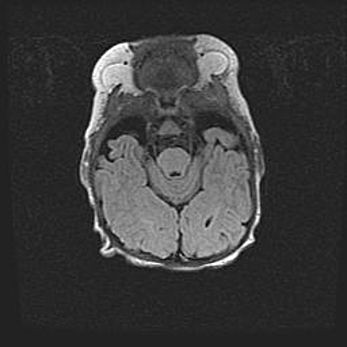

Наружная гидроцефалия с возможной атрофией височных областей.

Возраст: 28 дней

Вес: 3670 г

Пол: мужской

Окружность головы: 38 см

Срок гестации: 40 недель

Гидроцефалия головного мозга у новорожденных – это заболевание, которое характеризуется скоплением избыточного количества спинномозговой жидкости в желудочковой системе головного мозга в результате затруднения её перемещения от места выработки к месту поглощения в кровеносную систему или вследствие нарушения абсорбции. При открытой наружной форме гидроцефалии у новорожденных расширяются и переполняются субарахноидные пространства.

При нормотензивных  формах,  которые,  как  правило,  являются  следствием  перенесенных ишемических  повреждений  паренхимы  мозга,  возможно  сочетание микроцефалии  с нормотензивной гидроцефалией. В основе данных изменений лежит атрофия больших полушарий с преимущественной  локализацией  в  лобно-височных  областях.